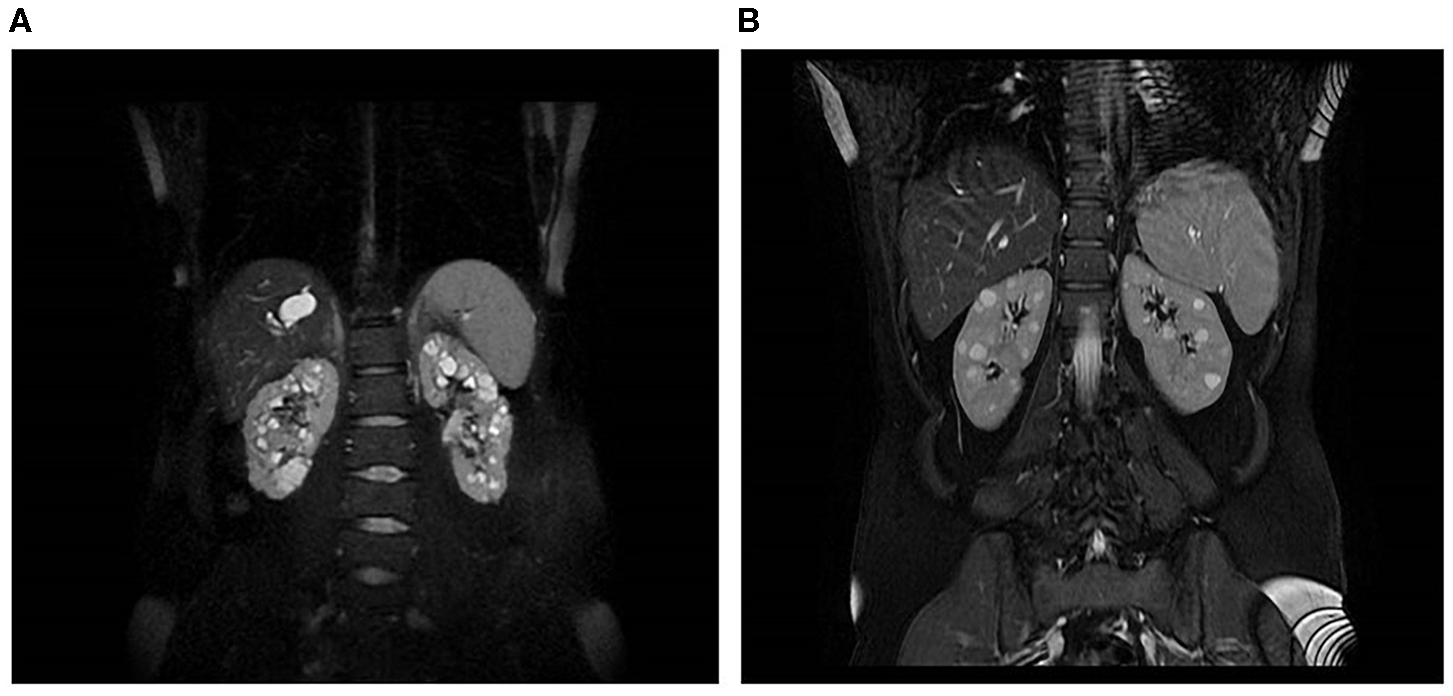

Patient 17316 carried compound heterozygous mutations in PKHD1, hence a diagnosis of ARPKD could be posed. She was a 31 years old woman who received a diagnosis of polycystic kidneys at 17. At 30, after her first pregnancy, she had proteinuria, multiple cysts in both kidneys and a mild reduction of GFR. No family members were reported to be affected by polycystic kidney and ADPKD gene testing resulted negative. An abdominal computed tomography scan showed, in addition to the known renal cysts, segmental dilatation of the intrahepatic bile ducts compatible with Caroli disease. PKHD1 analysis identified two mutations in compound heterozygosity, p.(Thr36Met) and p.(Cys2422Gly). MRI is shown in Figure 3A.

Figure 3. Kidney and liver images of two patients. (A) MRI of a 31-year-old woman with compound heterozygous mutations in PKHD1, who received a diagnosis of polycystic kidneys at 17. (B) MRI of a 45-year-old woman, who carried two heterozygous variants in PKHD1, p.(His3124Thr), and PMM2, p.(Gly42Arg).

Finally, patient 16542 was diagnosed with PKD at the age of 30 years, after the onset of arterial hypertension (MRI is shown in Figure 3B); she had normal renal function at last evaluation (45 years). Her father died at the age of 79, he had type 2 diabetes requiring insulin treatment, renal and hepatic cysts detected at ultrasonography and normal renal function. The patient carried a heterozygous variant of unknown significance in PKHD1, p.(His3124Tyr), defined as likely pathogenic in ClinVar, and a missense variant p.(Gly42Arg) in PMM2, classified as likely pathogenic. Recessive mutations in PMM2 were reported as associated to hyperinsulinemic hypoglycemia (HI) and PKD (Cabezas et al., 2017). The study of larger cohorts of patients will be able to define if the combination of variants in distinct recessive genes can be relevant for cysts progression.